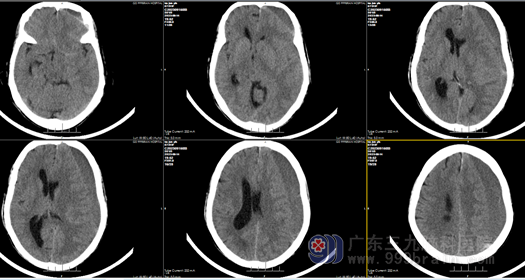

潮州市湘桥区一位柯奶奶,今年73岁,2023年6月在家不慎摔倒后昏迷,约5分钟后才缓缓醒来,苏醒后未太重视,也未将此事告知更多其他家属,其女儿要求柯奶奶去医院检查,老人家觉得没有任何不适,拒绝去医院检查。但9月初起,奶奶开始出现头晕,伴有右侧肢体乏力,呈进行性加重,只得到当地医院就诊,查头颅CT示“左侧额颞顶部慢性硬膜下血肿”。由于奶奶年龄大,当地医疗水平又有限,医生建议患者到省城就医。经多方打听,9月10日,患者来到广东三九脑科医院寻求进一步诊疗。

我院神经外十科欧阳辉教授接诊患者后,通过查体及详细询问其病史,结合患者颅脑CT 结果,诊断为“左侧额颞顶部慢性硬膜下血肿”,血肿如继续扩大,病情进展将有偏瘫可能,甚至会导改昏迷、脑疝。在患者入院后,欧阳辉教授带领团队进行了详细术前讨论与评估,最终确定了手术方案。向家属明确告知手术必要性和风险,获得充分理解并签字同意后,入院第2天外十科医生在全麻下行左侧慢性硬膜下血肿钻孔、冲洗,引流术”,手术顺利,患者手术后CT结果示:血肿已清除,柯奶奶术后很快神志清醒,言语对答切题,她未发生任何并发症和后遗症,手术3天后即可独立下床活动,伤口愈合良好,术后七天出院。回家后,奶奶又可以过上正常幸福的生活了。